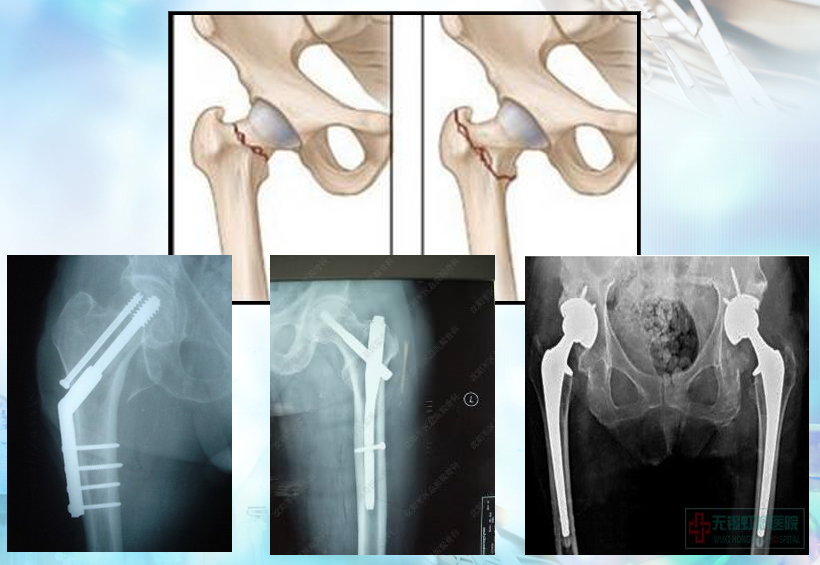

髋部骨折

一、髋部骨折患者术前翻身方法:

二、髋部骨折术后患者翻身方法:

三、全髋关节置换术后 (THR)病人翻身方法: